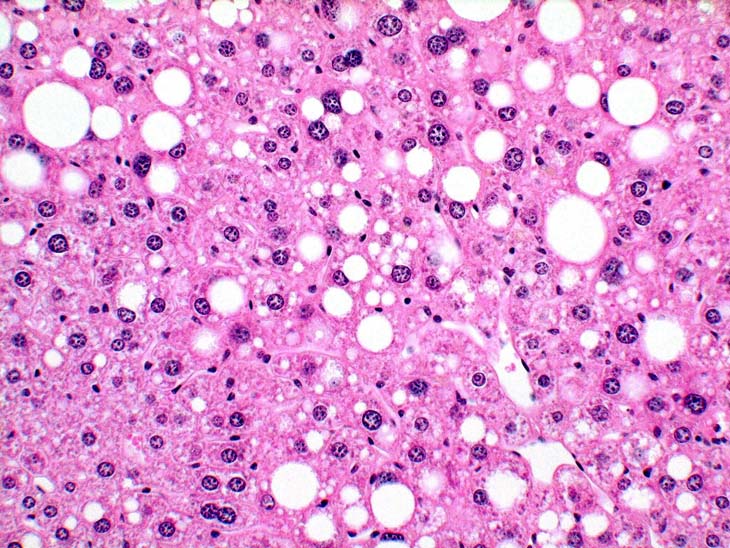

This example of fatty change represents a combination of microvesicular and macrovesicular fatty change with a distinct lobular pattern. The macrovesicular fat is localized at the periphery and probably represents condensation of microvesicular vacuoles.